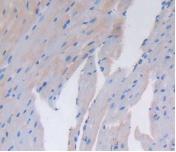

Figure. DAB staining on IHC-P; Samples: Mouse Heart Tissue.